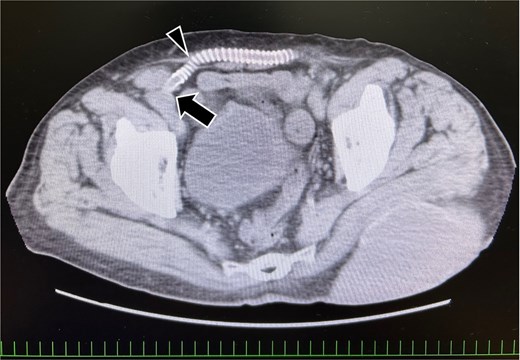

An 81-year-old man with a history of ilio-iliac artery bypass (Fig. 1) and left stent graft leg occlusion presented with swelling in the right lower abdomen. A diagnosis of right inguinal hernia was established (Fig. 2), and the patient was scheduled for surgical repair (Figs 3 and 4). Computed tomography revealed that the artificial vessel passed through the subcutaneous route, in which the artificial graft was anastomosed to the right external iliac artery in the preperitoneal space, and the subcutaneous tunnel (Fig. 1). Ultrasound imaging in the standing position revealed that the hernial sac originated lateral to the external iliac artery, hypogastric artery, and the point of origin of the artificial graft.

Preoperative computed tomography image showing the vessel graft on the right side. The external iliac artery and artificial vessel graft are anastomosed in the preperitoneal space (arrow). The graft running subcutaneously after originating from the abdominal wall (arrowhead).